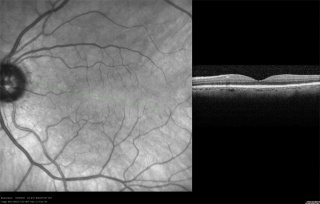

OCT imaging of the RNFL, ONH, and macula has been employed as a tool to aid in the diagnosis of glaucoma. A series of devices have been manufactured to analyze each of these components. Studies have demonstrated the high analytical and diagnostic performance of OCT imaging of the RNFL, ONH, and macula for the recognition of glaucomatous and non-glaucomatous eyes.[11]

General Concepts of OCT Analysis for Glaucoma[11]

- Circular scans are centered around the ONH in order to capture RNFL and ONH measurements.

- Based on the amount of light reflected between the outer edge of the RNFL and the internal limiting membrane (ILM), the thickness of the RNFL is captured on OCT.

- With regard to the Cirrus 5000 and Spectralis devices, the thickness of the neuroretinal rim is analyzed based on the minimum rim width (MRW), which is the distance from the ILM to the Bruch membrane opening (BMO). With regard to the 3D OCT-2000, the distance between the retinal pigment epithelium and the ILM is measured.

- Macular evaluation on OCT involves analysis of the ganglion cell - internal plexiform layer (GC-IPL) thickness, as well as analysis of the ganglion cell complex (GCC) that encompasses the RNFL, GC, and IPL.

- Analysis of the macula occurs within a rectangular area that is either centered on or near the fovea.

- Thickness measurements are often shown in a TSNIT (temporal, superior, nasal, inferior, temporal) orientation and are compared to age-matched controls.

- Age-matched control analysis generally utilizes the following criteria: the Green area is the 5th-95th percentile by age, the Yellow Area is 1st-5th percentile, and the Red Area is below the 1st percentile.